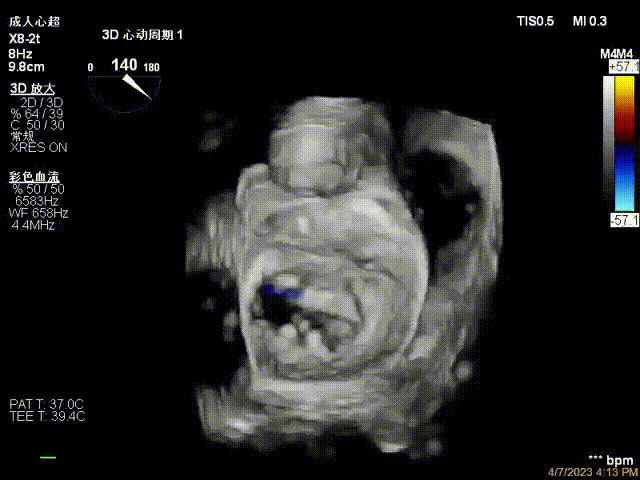

接受治療的是一例器質(zhì)性重度二尖瓣反流(DMR)患者,主訴“反復(fù)活動后胸悶,氣促3年余”。術(shù)前超聲顯示,雙房增大,二尖瓣脫垂伴重度反流,輕度三尖瓣反流,輕度肺高壓,升主動脈增寬。手術(shù)經(jīng)股靜脈-房間隔入路,采用全身麻醉插管,在TEE和DSA引導(dǎo)下完成房間隔穿刺。置入JensClip瓣膜夾系統(tǒng)后,在左房調(diào)整瓣膜夾的位置和軸向,后進(jìn)入左室,在TEE引導(dǎo)下捕捉二尖瓣前后瓣葉,并關(guān)閉瓣膜夾。經(jīng)TEE反復(fù)確認(rèn)手術(shù)效果后最終鎖定并釋放瓣膜夾。術(shù)后即刻超聲顯示瓣膜夾位置穩(wěn)定,功能良好,術(shù)前二尖瓣反流4+,術(shù)后0反流,肺靜脈逆流和左房壓都顯著好轉(zhuǎn),手術(shù)圓滿成功(以上數(shù)據(jù)都來源于醫(yī)院的臨床記錄)。術(shù)后患者狀態(tài)良好,目前已安排出院。

術(shù)后超聲顯示二尖瓣反流消失,瓣膜夾穩(wěn)定